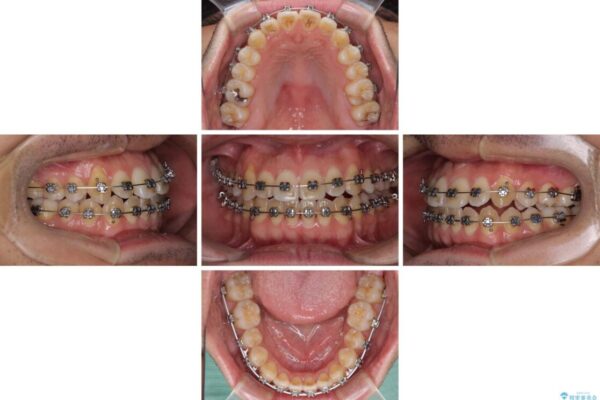

治療途中

• 左右の八重歯が気になる ワイヤー装置での咬み合わせ改善 治療途中画像